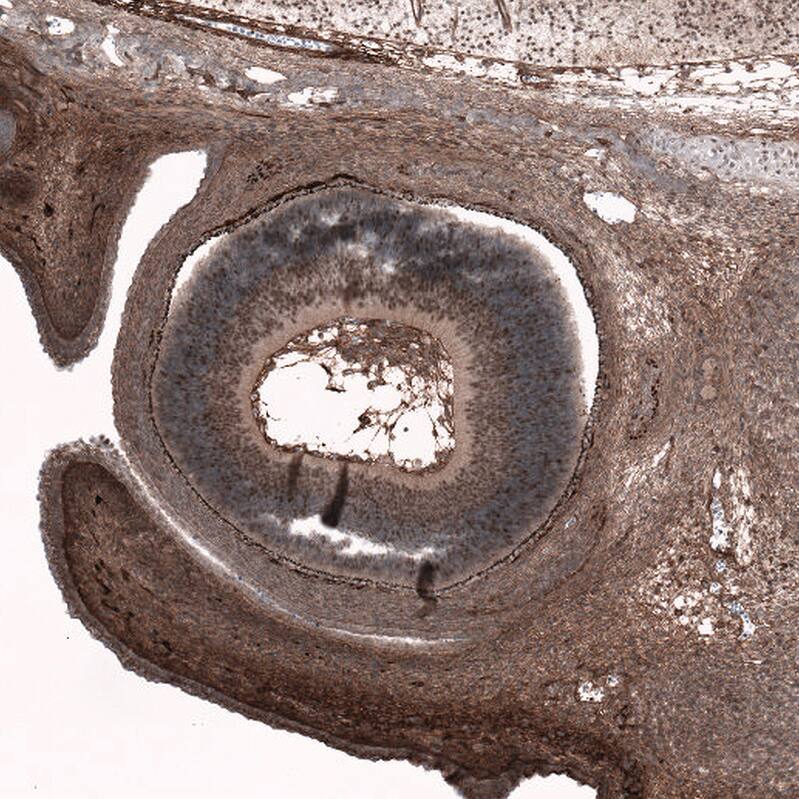

Staining of human chronic lymphocytic leukemia shows no nuclear positivity in tumor cells as expected.

Staining of human mantle cell lymphoma shows moderate to strong nuclear positivity in tumor cells.